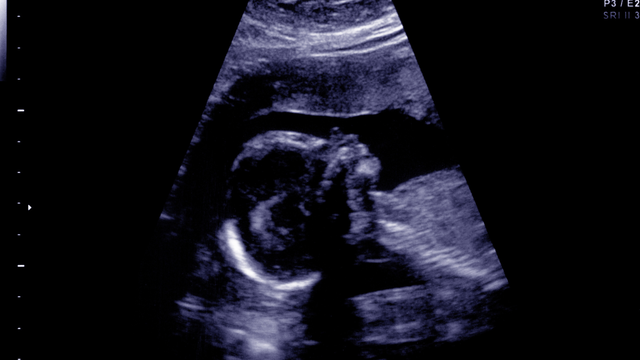

Sự phát triển của thai nhi